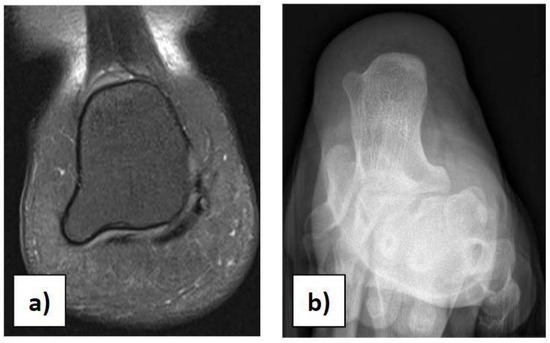

In the case of children with heel pain, it is important to perform a proper clinical assessment to make a suitable differential diagnosis, excluding traumas, occult or stress fractures, osteochondrosis, calcaneo-navicular or talo-calcaneal coalition, anatomical variations, rheumatologic conditions, infections, benign neoformations, and malignant neoformations. Anatomical variations in the calcaneus should be considered in the case of palpation of masses during physical examination [21]. We had a case of a 12-year-old girl with an incidental X-ray and MRI finding of a painless 7 × 8 mm bilateral symmetric bony mass on the infero-lateral aspect of both calcanei, without a cartilaginous cap (Figure 3a,b). She could play all sports and wear footwear without any problems and did not need any orthopaedic treatment.

Figure 3.

(a) Anatomical variation in the calcaneus on MRI. (b) Anatomical variation in the calcaneus on X-ray.